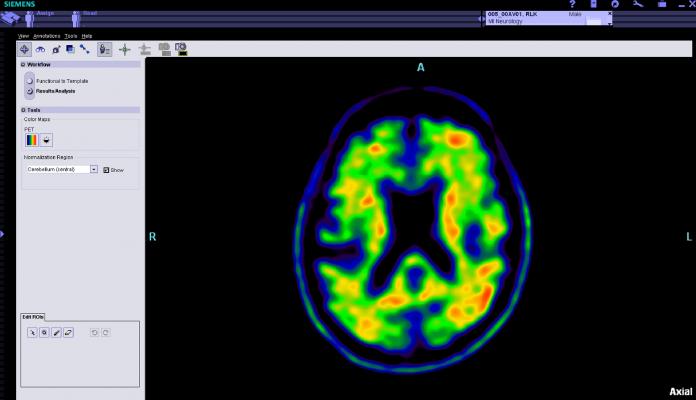

Image courtesy of Siemens Healthcare

18F NaF is indicated for PET bone imaging to define areas of altered osteogenic activity in the body, including metastatic bone disease from cancer. Multiple clinical studies have demonstrated improved sensitivity and specificity of PET/computed tomography (PET/CT) imaging compared to single-photon emission computed tomography (SPECT)/planar bone imaging. Early identification of patients at higher risk for developing bone metastases enables practitioners to be proactive in their diagnosis and treatment.